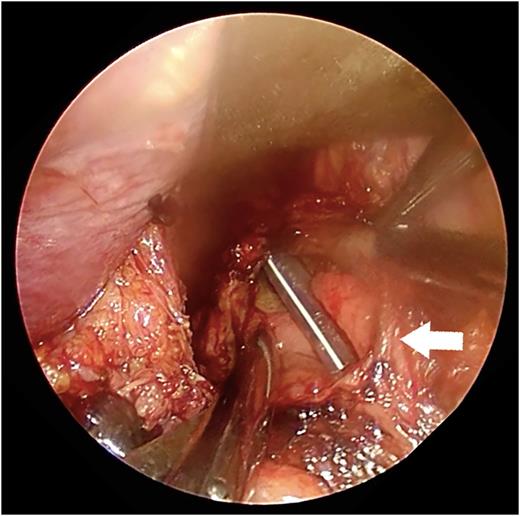

A 67-year-old man presented with vomiting and epigastric pain. He had a history of duodenal ulceration and emergent laparotomies for repeated duodenal perforation, resulting in stenosis of the second portion of the duodenum. The patient was referred to our hospital for evaluation of vomiting. He exhibited upper abdominal guarding on physical examination. His blood chemistry revealed no abnormal findings with the exception of a mild increase in the C-reactive protein level (2.1 mg/dl). His nutritional state was maintained. Dynamic computed tomography revealed massive right pleural effusion with pneumomediastinum. A defect was present in the lower esophagus, his stomach was dilated and the proximal duodenal wall was thickened (Fig. 1a and b). Thoracoscopic exploration was performed prior to laparotomy in the left semi-lateral decubitus position with 2 ports under differential lung ventilation. The right pleural cavity was severely contaminated with brownish pleural effusion and was thus irrigated under thoracoscopy, but the perforated site was not identified. Laparotomy was then performed, which revealed a 4-cm longitudinal defect on the right side of the lower esophagus via esophageal hiatus (Fig. 2). The defect was closed by direct suturing with 4-0 pieces of monofilament strings and reinforced by using the greater omentum. The surgical field was irrigated, and a feeding jejunostomy was created. A 19F blake drain (Ethicon, Inc., Sommerville, NJ, USA) was placed in the lower mediastinal space via abdominal cavity, and a 20F thoracic drain (Sumitomo Bakelite Co., Ltd, Tokyo, Japan) was placed in the right thoracic cavity via the port site. The position of the mediastinal drain was cranially adjusted using the thoracoscopy (Fig. 3a and b). Extubation and enteral feeding via the jejunostomy tube were initiated on Day 2. Endoscopic dilatation was performed due to esophageal stenosis. The patient was discharged on Day 60 without mediastinitis, pneumonia or empyema.

Thoracoscopic mediastinal drainage. (a) The angle of the drain was too steep at first. (b) The drain was successfully inserted in the deepest region of the chest by adjusting the angle of the drain.